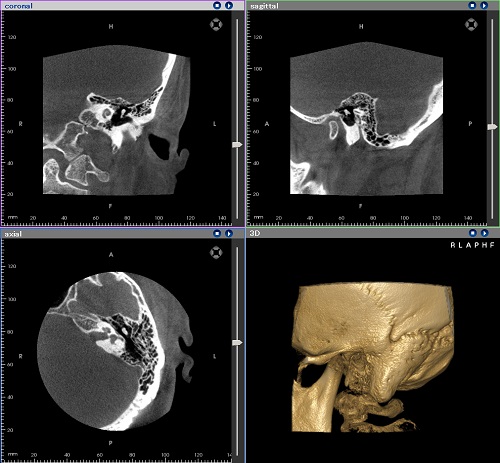

- 耳鼻科用CTを導入しております

- 耳鼻科用CTを導入することで、耳や鼻などの病変の診断の際に、数㎜単位で鮮明に写すため、より正確に診断をすることが可能になりました。これまで、医療センターなどに紹介し、CT撮影に行ってもらっていましたが、導入により迅速にCT撮影ができるようになりました。